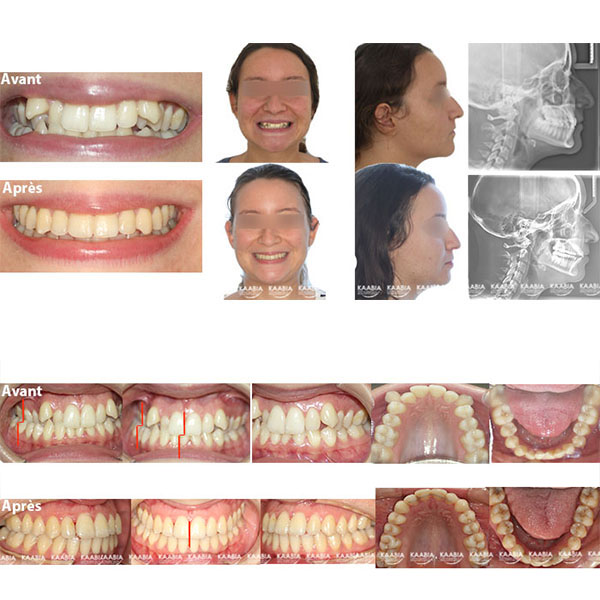

Syndrome de Cauhepe et Fieux

Cas A syndrome de Cauhepe et Fieux

Cas B syndrome de Cauhepe et Fieux

Cas C syndrome de Cauhepe et Fieux

Cas D syndrome de Cauhepe et Fieux

Cas E syndrome de Cauhepe et Fieux

Cas F syndrome de Cauhepe et Fieux

Syndrome de CAUHEPE et FIEUX / ESHLER